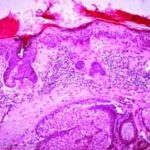

This variety of keratosis, sometimes referred to as florid keratosis, may easily be overdiagnosed as invasive squamous cell carcinoma by the unwary. Mild or moderate papillomatosis may be present. The epidermis is thickened in most areas and shows irregular downward proliferation that is limited to the uppermost dermis and does not represent frank invasion .A varying proportion of the keratinocytes in the stratum malpighii show a loss of polarity and thus a disorderly arrangement. Some of these cells show pleomorphism and atypicality (“anaplasia”) of their nuclei, which appear large, irregular, and hyperchromatic. Often the nuclei in the basal layer are closely crowded together. Some of the cells in the midportion of the epidermis show premature keratinization, resulting in dyskeratotic cells or apoptotic bodies characterized by homogeneous, eosinophilic cytoplasm with or without a nucleus. In contrast to the epidermal keratinocytes, the cells of the hair follicles and eccrine ducts that penetrate the epidermis within actinic keratoses retain their normal appearance and keratinize normally. Occasionally, cells of the normal adnexal epithelium extend over the atypical cells of the epidermis in an umbrella-like fashion. In some cases, abnormal keratinocytes extend downward on the outside of the follicular infundibulum to the level of the sebaceous duct and, less commonly, along the eccrine duct . |

In rare instances of actinic keratosis of the hypertrophic type, in addition to finding anaplastic nuclei in the lower epidermis, one finds areas of epidermolytic hyperkeratosis in the upper epidermis. These changes are like those seen in bullous congenital ichthyosiform erythroderma, in linear epidermal nevus, and as incidental epidermolytic hyperkeratosis in a variety of lesions. In areas of epidermolytic hyperkeratosis, one observes in the upper epidermis clear spaces around the nuclei and a thickened granular layer with large, irregularly shaped keratohyaline granules (39). Epidermolytic hyperkeratosis may occur also in lesions of solar cheilitis . |

In the atrophic type of actinic keratosis, hyperkeratosis usually is slight. The epidermis is thinned and devoid of rete ridges. Atypicality of the cells is found predominantly in the basal cell layer, which consists of cells with large hyperchromatic nuclei that lie close together. The atypical basal layer may proliferate into the dermis as buds and ductlike structures. It may also surround as cell mantles the upper portion of pilosebaceous follicles and sweat ducts, the epithelium of which otherwise appears normal . |

The bowenoid type of actinic keratosis is histologically indistinguishable from Bowen’s disease and may also be referred to as squamous cell carcinoma in situ. As in Bowen’s disease, within the epidermis there is considerable disorder in the arrangement of the nuclei, as well as clumping of nuclei and dyskeratosis